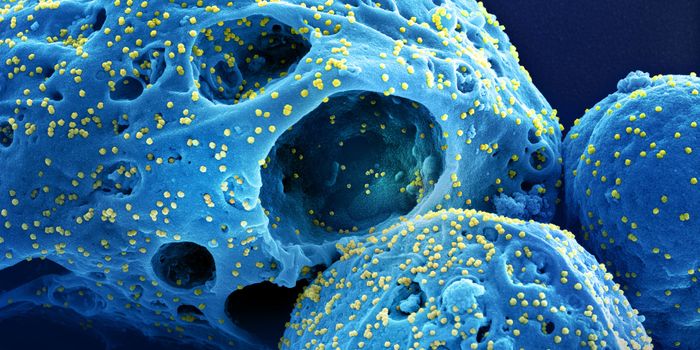

AUG 24, 2020ImmunologyOnce in the body, HIV tracks down T cells that bear the CD4 receptor. It attaches to these immune cells, fusing itself w ...

JUL 19, 2016CancerA decade-old technology to arm the immune system to fight cancer is now being adapted to fight HIV, one of the most pern ...

NOV 17, 2020ImmunologyLast year, around 1.7 million people became infected with HIV, with around half of these being women. Encouraging result ...

MAR 06, 2019Health & MedicineThere is a consensus that the first HIV infection occurred in the 1920s in Kinshasa, the Democratic Republic o ...

AUG 14, 2022ImmunologyFor the second time this year and only the fourth time ever, researchers have announced that a person has been cured of ...

APR 05, 2016Health & MedicineIn an effort to understand how HIV evolves resistance to drugs, scientists have found that it may be possible to steer t ...

MAY 23, 2024MicrobiologyWhen human immunodeficiency virus (HIV) emerged and was identified as the cause of acquired immunodeficiency syndrome (A ...

FEB 17, 2020ImmunologyYears of work and over $100 million in study costs have been abandoned after an HIV-vaccine tested in South Africa faile ...

JUN 04, 2016Clinical & Molecular DXA new study report found that at least 2,234 people contracted the human immunodeficiency virus (HIV) from blood transfu ...

JUL 10, 2020Drug Discovery & DevelopmentPharmaceutical company ViiV Healthcare has announced that its long-lasting, injectable drug, cabotegravir, is more effec ...